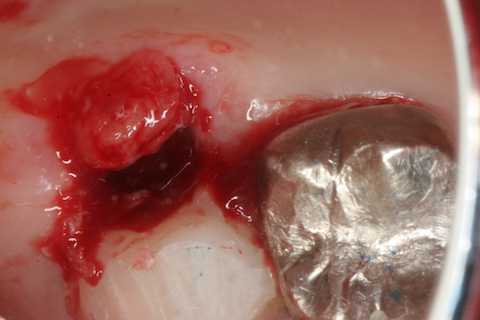

今日の抜歯再植術シリーズ39.2 2025.11.15